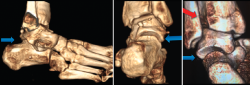

Por otro lado, conocemos que existen otras secuelas, como complicaciones de los esguinces de tobillo. En ocasiones, pasa desapercibido el llamado “esguince alto”, cuyos síntomas alrededor de la sindesmosis pueden producir consecuencias degenerativas, al variar el pico de presiones sobre las superficies articulares implicadas en el tobillo. Mediante una carga axial y rotación externa mantenida con el uso de este dispositivo de carga simulada y, tras unos cortes axiales de TC comparados de ambos tobillos, es posible medir las variables de rotación del peroné, así como una traslación posterior en el plano sagital, evidenciando una inestabilidad de la articulación tibioperonea distal. No en pocas ocasiones esta lesión viene asociada a la rotura del ligamento peroneoastragalino anterior (PAA), por lo que su reparación aislada podría estar abocada al fracaso (Figura 7).

Figura 7. A: radiografías en carga de un paciente con inestabilidad crónica del tobillo derecho; B: tomografía computarizada (TC) en descarga bilateral del mismo paciente; C: imagen de la posición durante la TC dinámica en carga simulada, eversión y rotación externa forzada; D: nótese la inestabilidad de la articulación tibioperonea distal durante la carga (flecha azul); E: relación entre peroné y astrágalo en este paciente con inestabilidad de tobillo y afectación de la articulación tibioperonea. Nótese la posición posterior del peroné y la rotación externa (flecha roja).